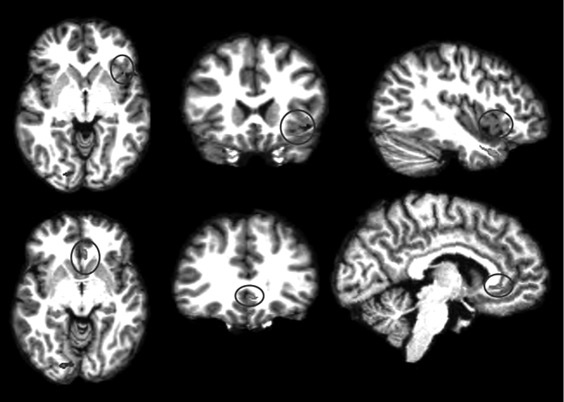

Анализируя далее научную литературу, мы пришли к выводу, что процесс поведенческого подражания с участием верхних отделов височной коры и эмоциональный (физиологический) резонанс, требующий участия островка, тоже имеют отношение к системе зеркальных нейронов. При подражании верхние отделы височной коры кодируют сложные процессы сенсорных следствий двигательных актов; при эмоциональном резонансе островок осуществляет физиологический и аффективный сдвиг, имитирующий его у другого человека. Исходя из параллелизма этих функций реципрокного действия (имитационной, физиологической и аффективной), мы можем использовать термин «резонансный контур», подразумевая, что в нем могут участвовать зеркальные нейроны, но не все компоненты этого контура двигательные, поэтому формально мы не можем назвать такой контур зеркальным. В нашем обсуждении мы примем во внимание это отличие и будем называть резонансный контур именно так, или будем прибегать к выражению «области, связанные с системой зеркальных нейронов» (рис. П.1 и П.2).

П.2

Иллюстрация к книге — Внимательный мозг. Научный взгляд на медитацию [i_015.jpg]

Рис. П.1, П.2. Функциональная МРТ, выполненная во время выполнения медитации осознавания дыхания. На снимках видна активация верхней височной извилины (рис. П.1) и активация островка и вентрального отдела передней поясной извилины (рис. П.2). Верхняя височная кора, островок и области срединной префронтальной коры (показанные здесь) вместе с системой зеркальных нейронов, как предполагается в тексте, содержат элементы «резонансного контура», которые активируются в ходе внимательного осознавания (снимки напечатаны с разрешения Сары Лазар © 2005)